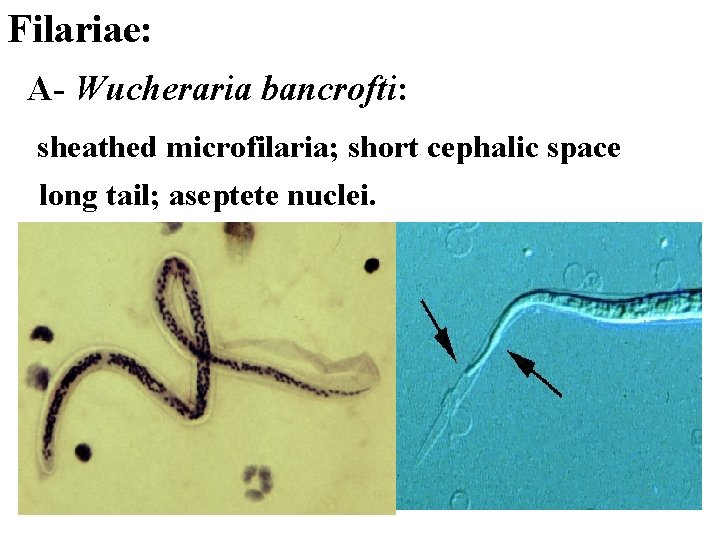

Filariae: A- Wucheraria bancrofti: sheathed microfilaria; short cephalic space long tail; aseptete nuclei.